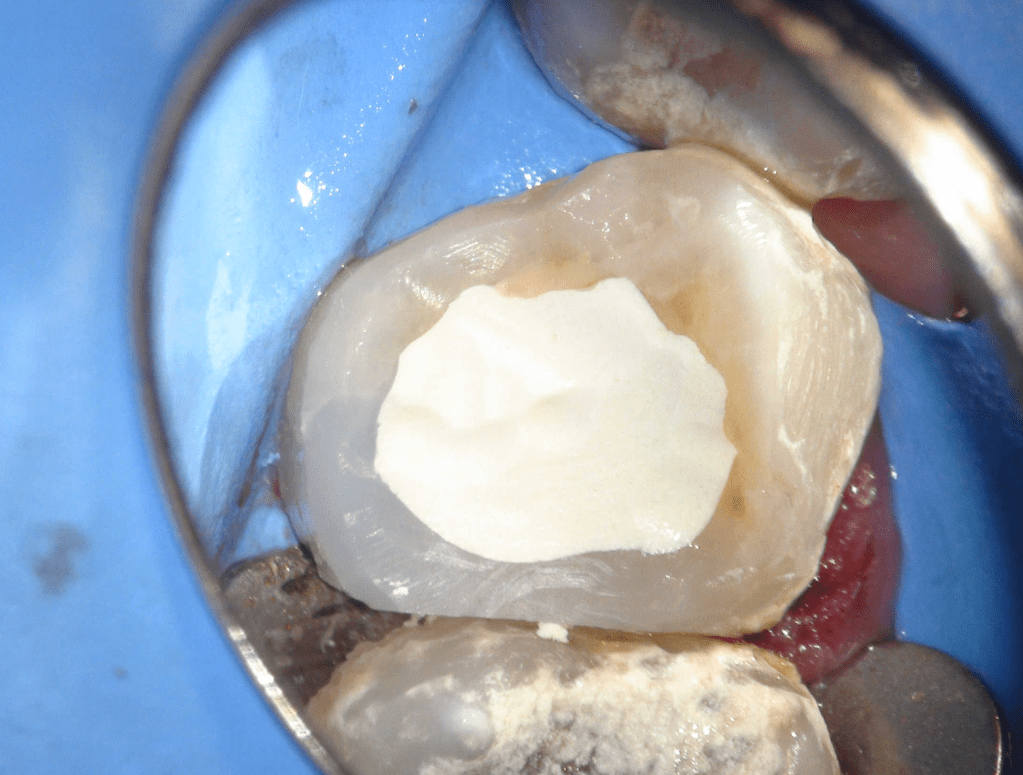

Pulpotomía biodentine + reco preendio